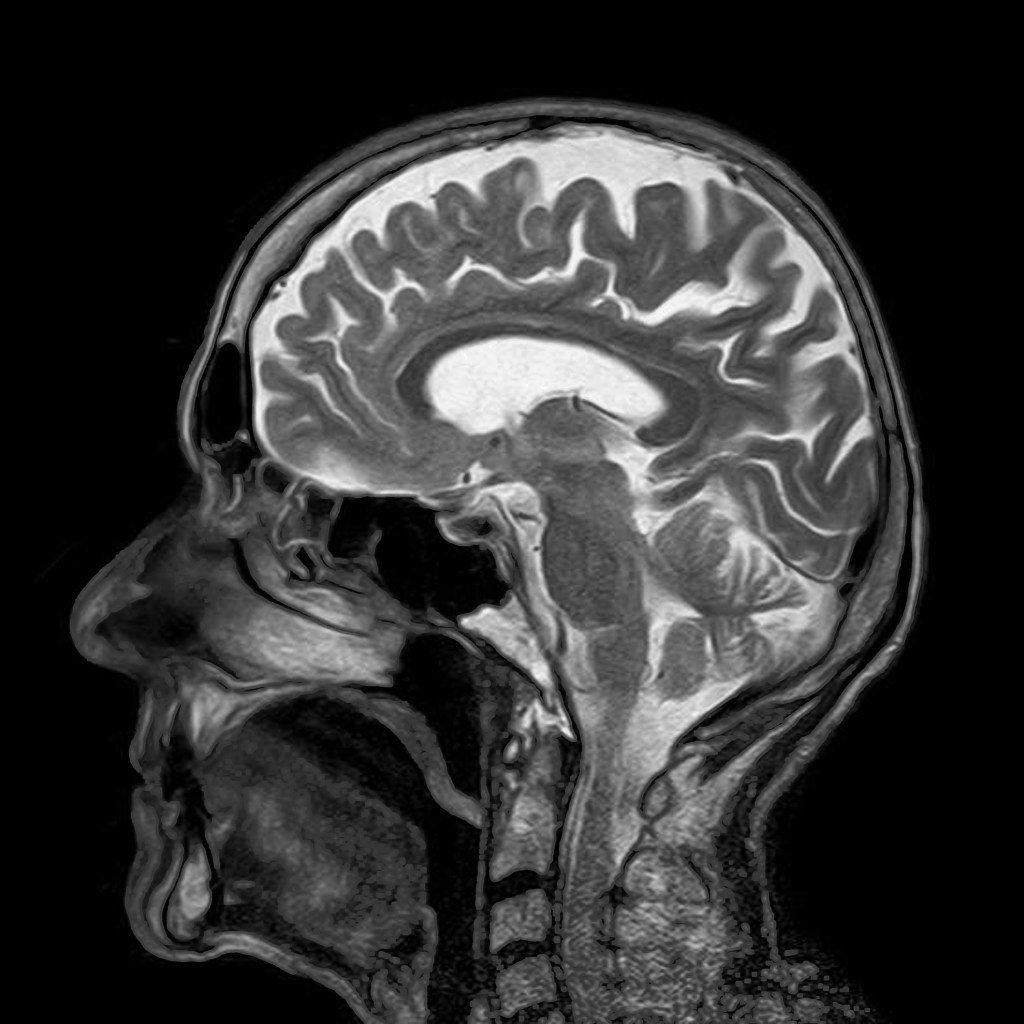

MRI image by toubibe from Pixabay

One of the most exciting ways to use computers to look into our bodies is called magnetic resonance imaging (MRI). While X-rays are very useful they only work when dense materials in the body absorb the X-rays energy (this loss of energy as they pass through the body is called attenuation). But lots of interesting stuff in our innards isn’t dense or filled with attenuating materials. We are after all flesh and blood, and those don’t show up on X-rays. Enter the magnet, or to be precise the proton. Water makes up the majority of structures in our body, and water has an interesting property. In a high magnetic field the protons in the hydrogen act like atomic magnets, and line up with (align with) the applied external magnetic field, like soldiers all standing to attention.

So how does this let us image inside bodies? In an MRI (Magnetic Resonance Image) scanner we have a big external magnetic field, and on top of this we add a smaller magnetic gradient across the body. That means each location across the body has a different local magnetic field. We then apply a radio pulse, at a range of resonant frequencies, and for each pulse we measure how much signal we get back. From this we can reconstruct an image of the water (proton) distribution across the body. We can also use tomographic techniques: by simply rotating the magnetic gradient around the body, we produce a 3D slice. The water content is different in different body tissues, so the scan shows us all the soft interesting stuff, where it is and what shape it’s in. Better still the way that the protons realign after they have been toppled is dependant on the chemicals round them, so we can even get some data on that too by looking at the speed at which they realign and give off their energy.